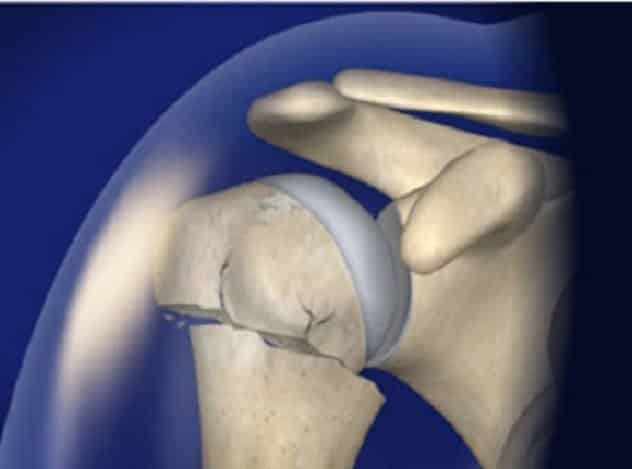

Эндопротезирование плечевого сустава

Если из-за травмы произошло раздробление плечевой кости и развивается асептический некроз головки, больному делают эндопротезирование. Для выполнения операции используют однополюсные или тотальные эндопротезы. Тип протеза подбирает врач соответственно возрасту пациента и состоянию его здоровья.

Внимание. Некоторым больным противопоказано эндопротезирование. Тогда им делают артродез — операцию по закреплению сустава в неподвижном положении.